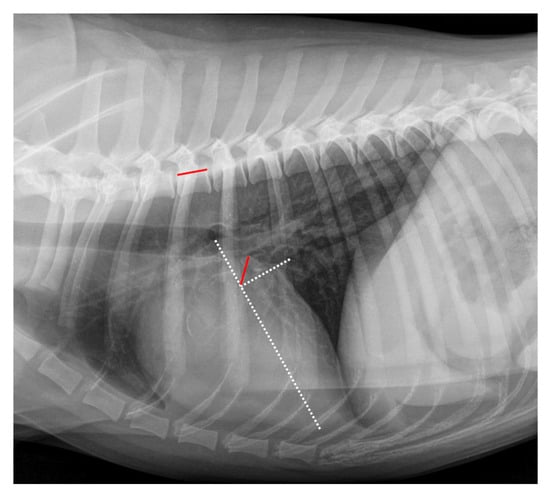

2.4. Radiographic Measurements